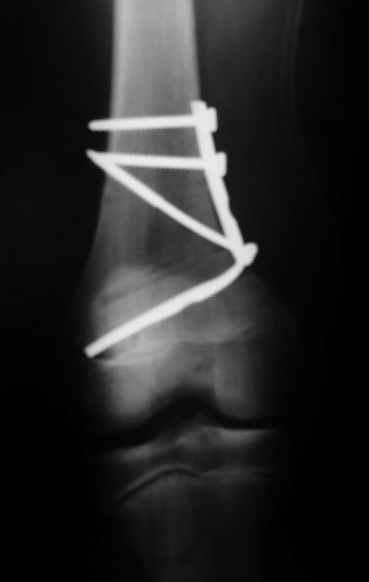

Как вариант решения прогрессирующей вальгусной деформации коленного сустава я бы предложил косую остеотомию дистального отдела бедра с фиксацией пластиной и компрессирующим винтом.

Взгляните на снимки , может быть это вам поможет.

Около 5 лет применяю этот тип дистальной остеотомии бедра для коррекции механической оси Н/К ( более 20 случаев) - достаточно эффективная операция.

Было одно осложнение у молодого пациента - ятрогенное повреждение бедренной артрерии, которое решилось васкулярной пластикой без каких -либо последствий для функции конечности.